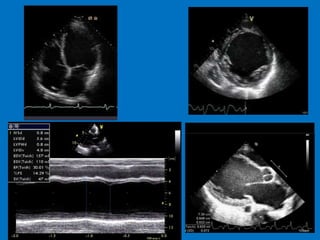

• 2 D - Echo

SEGMENTAL WALL MOTIONABNORMALITIES IN DILATED CARDIOMYOPATHY • Regional wall motion abnormalities observed in at least 50% of patients with non-ischemic causes of dilated cardiomyopathy • Most frequent wall motion abnormalities: – anterior wall & apex • Posterior and lateral walls most likely to be preserved • Type of abnormality: – hypokinesis (83%) – akinesis (11%) – dyskinesis (6%) • Heterogeneity in regional oxidative metabolism using C- 11 acetate clearance has been demonstrated in DCM AJC 1990;65:364-70; Arch Int Med 1992;152:769-72; JACC 1995;25:1258-62